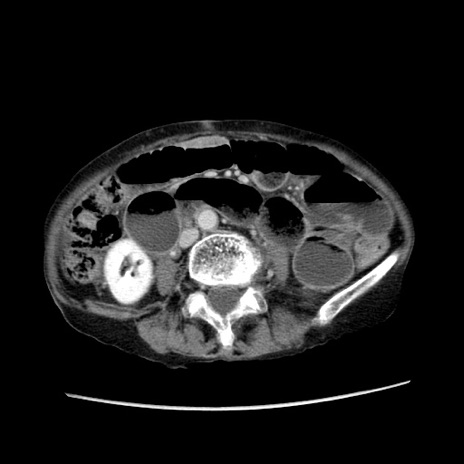

冠状断像

症例25(横断像)

【症例】80歳代女性

【主訴】胸のつかえ感

【現病歴】約9時間前に食後から胸のつかえた感じあり、嘔吐あり、来院。

【既往歴】胃癌(全摘)、胆摘、虫垂炎

【身体所見】心窩部に圧痛あり、反跳痛なし。

【データ】WBC 5700、CRP 0.05